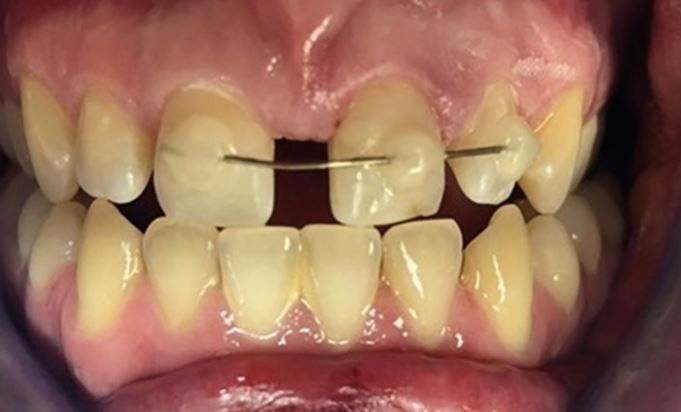

After replantation, teeth need dental splinting and ideally in a surgery, but possibly on-site if facilities allow. Common splinting techniques are described from composite and orthodontic wire (<0.4 mm diameter) to novel approaches using fishing line or suturing across teeth.49 Splints should be easy to apply and remove, not interfere with occlusion, and allow access for endodontic treatment and oral hygiene measures (Fig. 19).

An orthodontic wire and composite dental trauma splint